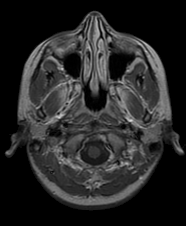

Stack image, image-set 불러오기 소개 동영상 Stack image 불러오기 위의 이미지는 인간의 뇌를 MRI(자기공명영상장치)로 촬영한 영상입니다. ( 위 이미지는 본 블로그 맨밑 출처 1에 가셔서 다운로드 받을 수 있습니다.) 인간의 뇌를 수평방향 섹션으로 layer별로 imaging 한것을 하나의 이미지 파일로 담았고, 이것을 stack image 이라고 합니다. 따라서 하나의 stack image에는 여러개의 layer 또는 frame 이미지를 저장하고 있습니다. 대상 이미지의 세부정보, 예를들어 layer의 수, 이미지의 너비, 높이 등을 알기위해 imfinfo( ) 명령어를 사용하였고, 모든 layer 데이터를 하나의 변수에 저장하기 위해 imgSet 변수를 생성하였습니다. 각..